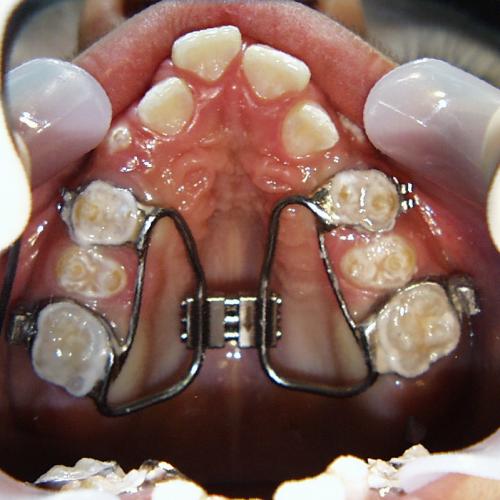

Beim nächsten Fallbeispiel war der Oberkiefer deutlich zu schmal im Verhältnis zum Unterkiefer, der Biß war frontoffen und die oberen Schneidezähne standen sehr unregelmäßig bei einer auffallenden Mittenverschiebung nach links.

Vor der Behandlung

Zunächst wurde der obere Zahnbogen geweitet und mit dem Ausrichten der Schneidezähne begonnen.